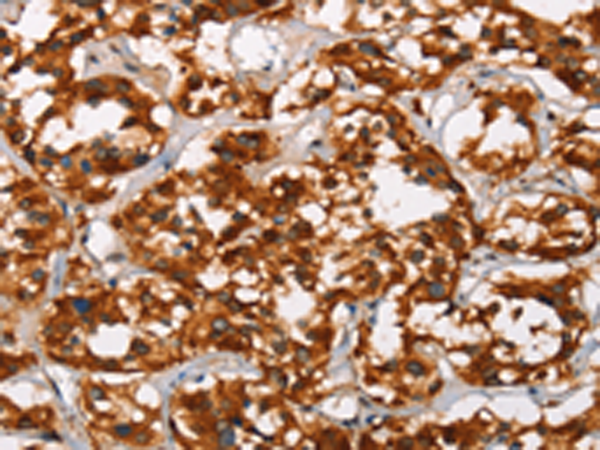

分类: 科研抗体货号: P11581别名: APS应用: IHC反应种属: Human, Rat